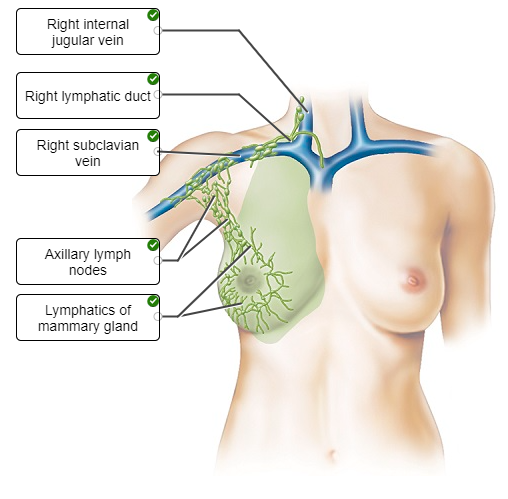

Label the figure showing the pathway for lymphatic drainage from the right breast.